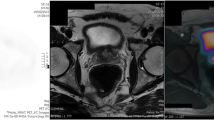

Subjects underwent 1.5T magnet mpMRI (Avanto, Siemens, Erlangen, Germany) with pelvic-phased array coil, following intravenous spasmolytic (Buscopan; Boehringer Ingelheim, Germany) 0.2 mg/kg (maximum 20 mg) to minimize bowel peristalsis. Full mpMRI parameters are given in Table 2. Figure 1 shows an example mpMRI with a significant TZ tumour.

Demonstrates single slice axial images of significant tumours (arrow): (a) T2 weighted; (b) ADC map; (c) pre-contrast T1 weighted; and (d) early post contrast T1 weighted images in a 74-year-old patient with an anterior right transition zone tumour (Gleason 3 + 4; maximum cancer core length 11 mm) prior to transition zone contouring and histogram analysis